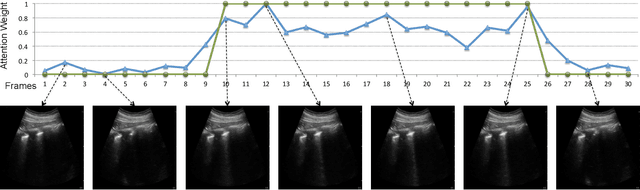

Abstract:Lung ultrasound (LUS) imaging is used to assess lung abnormalities, including the presence of B-line artefacts due to fluid leakage into the lungs caused by a variety of diseases. However, manual detection of these artefacts is challenging. In this paper, we propose a novel methodology to automatically detect and localize B-lines in LUS videos using deep neural networks trained with weak labels. To this end, we combine a convolutional neural network (CNN) with a long short-term memory (LSTM) network and a temporal attention mechanism. Four different models are compared using data from 60 patients. Results show that our best model can determine whether one-second clips contain B-lines or not with an F1 score of 0.81, and extracts a representative frame with B-lines with an accuracy of 87.5%.